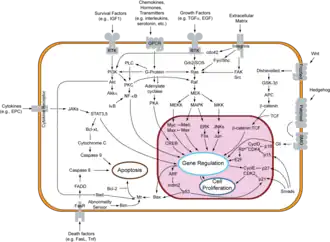

Signaltransduktionswege

Der Vorgang der Apoptose lässt sich in zwei Phasen unterteilen: Initiations- und Effektorphase.

Initiationsphase

In der Regel werden hinsichtlich der Initiationsphase zwei Vorgänge unterschieden: der extrinsische (Typ I) und der intrinsische (Typ II) Weg.[10][11] Eine strikte Trennung der Vorgänge ist in vivo kaum möglich.[10]

Extrinsischer Weg – Typ I

Der extrinsische Weg wird eingeleitet durch Ligandenbindung an einen Rezeptor der TNF-Rezeptorfamilie (z. B. CD95 oder TRAIL). Diese sogenannten Todesrezeptoren besitzen in ihrem zytoplasmatischen Teil eine Todesdomäne (DD, „death domain“). Liganden sind zum Beispiel der Tumornekrosefaktor (TNF) und andere Zytokine, die beispielsweise von T-Lymphozyten abgesondert werden.

Durch die induzierte Trimerisierung des Rezeptors bilden die Todesdomänen eine Struktur, an die nun Adaptermoleküle mit eigener Todesdomäne durch homotypische Interaktionen binden können. In einem ersten Schritt wird das „TNF-Rezeptor-assoziierte Protein“ (TRADD) rekrutiert. Anschließend bindet an die DD des TRADD das „Fas-assoziierte Protein mit Todesdomäne“ (FADD). FADD besitzt neben der DD auch eine Todeseffektordomäne (DED, „death effector domain“), über die die proCaspase 8 mit ihrer DED an den Komplex bindet. Diese kann sich nun durch die entstandene hohe lokale Konzentration autokatalytisch aktivieren. Die aktive Caspase 8 löst ihrerseits die sogenannte Caspase-Kaskade aus, wodurch in einer signalverstärkenden Rückkopplung weitere Caspase-8-Moleküle aktiviert werden.

Intrinsischer Weg – Typ II

Beim intrinsischen Weg oder der Apoptose des Typs II kommt es durch noch nicht genau bekannte Mechanismen zur Freisetzung von Cytochrom c und anderen pro-apoptotischen Faktoren wie Smac/DIABLO aus den Mitochondrien in das Zytoplasma. Dieser Weg kann ausgelöst werden durch Tumor-Suppressoren, wie beispielsweise p53, einem Transkriptionsfaktor, der durch Schädigung der DNA aktiviert wird. p53 stimuliert die Expression pro-apoptotisch wirkender Mitglieder der Bcl-2 Familie (z. B. Bax, Bad). Diese führen dann zur Freisetzung der pro-apoptotischen Faktoren – wie etwa Cytochrom c – aus dem mitochondrialen Intermembranraum. Jedoch wirken viele toxische Substanzen, wie z. B. Chemotherapeutika, auch direkt auf die Mitochondrien und können so die Typ-II-Apoptose induzieren. Die Bindung von Cytochrom c und dATP an Apaf-1 (apoptotischer Protease-Aktivierungsfaktor-1) bewirkt eine Konformationsänderung des Proteins. Durch diese Konformationsänderung wird die Proteinbindedomäne CARD (Caspase-Rekrutierungs-Domäne) von Apaf-1 zugänglich, so dass sie an die CARD Domäne der Procaspase 9 binden kann. Die Bildung dieses Heterodimers ist eine Voraussetzung für die autolytische Aktivierung der Caspase 9. Dieser Komplex wird Apoptosom genannt und stellt die aktive Form der Caspase 9 dar. Analog zu Caspase 8 initiiert aktive Caspase 9 die Caspase-Kaskade. Eine Signalverstärkung dieses Weges wird innerhalb der Caspase-Kaskade durch Caspase 7 vermittelt, welche nicht nur Substrate spaltet, die an der Ausführung der Apoptose beteiligt sind, sondern ihrerseits auch die Caspase 9 aktiviert.

Zellen, die vielleicht auf Grund einer zu geringen intrazellulären Menge an Caspase 8 nicht die Typ-I-Apoptose zu initiieren vermögen, können den mitochondrialen Weg zur Signalverstärkung aktivieren. Dazu spaltet die Caspase 8 das zytosolische Protein Bid („BH3 interacting domain death agonist“). Das entstehende C-terminale Spaltprodukt tBid („truncated Bid“) vermittelt nach der Translokation in die Mitochondrien die Freisetzung von pro-apoptotischen Faktoren und führt zur Aktivierung der Caspase 9.

Stressinduzierter Weg – Typ III

Stressreaktionen des Endoplasmatischen Retikulums, die beispielsweise durch deregulierte Entleerung des ER-Calciumspeichers, Glucosemangel, Hypoxie oder missgefaltete Proteine (Unfolded Protein Response) hervorgerufen werden können, können Apoptose initiieren. Es gibt dabei einen Transkriptionsfaktor- und einen Caspase-abhängigen Signalweg.[12][13][14][15]

Ausführungsphase und Caspase-Kaskade

Sogenannte Effektorcaspasen, vornehmlich die Caspasen 3, 6 und 7, führen zum apoptotischen Tod der Zelle. Sie sind selbst aktiv am Abbau von Lamin (in der Zellkernmembran) und Actin (Teil des Zytoskeletts) beteiligt. Andererseits aktivieren sie sekundäre Zielproteine (z. B. Caspase aktivierte DNase, CAD, oder andere Caspasen) durch limitierte Proteolyse. Die DNase spaltet genomische DNA an internukleosomalen gekennzeichneten Regionen (linker region) und produziert 180–185 bp Fragmente. Dieses charakteristische Längenmuster lässt sich in einer Agarose-Gel-Elektrophorese als „Apoptoseleiter“ darstellen. Die Darstellung der „Apoptoseleiter“ ist deshalb eine sensitive Methode, um Apoptose vom ischämischen oder toxischen Zelltod abzugrenzen. Ein weiterer Aspekt ist die caspasevermittelte Unterdrückung der DNA-Reparatur.

Letztlich schnürt die Zelle nach und nach kleine Vesikel ab, die wiederum durch spezialisierte „Fresszellen“ (Phagozyten) aufgenommen werden. Im Gegensatz zur Nekrose bleibt hierbei die Zellmembran intakt.

Der Austritt von Cytochrom c aus Mitochondrien ins Zytoplasma, der ein allgegenwärtiges Anzeichen für Apoptose ist, tritt beim extrinsischen Weg erst spät während der Apoptose auf und ist eher Resultat der Apoptose als ihr Auslöser.

Beim extrinsischen Weg unterscheidet man ferner zwischen aktiver (durch Aktivierung von Rezeptoren induziert) und passiver (ausgelöst durch Entzug von Wachstumsfaktoren, z. B. Neurotrophine) Apoptose.

Die wichtigsten bei der Unterdrückung der Apoptose beteiligten Proteine sind die anti-apoptotischen Mitglieder der Bcl-2 Familie (Bcl-2 und Bcl-xL) und die IAPs (Apoptose-inhibitorische Proteine, engl. inhibitor-of-apoptosis proteins), wie beispielsweise Survivin. Weiter stromaufwärts liegen die Proteinkinase B (Alternativbezeichnung: Akt), z. B. in Zusammenhang mit Rezeptoren der Trk-Familie (siehe Neurotrophin) und Transkriptionsfaktoren der FOXO-Familie sowie der Transkriptionsfaktor NF-κB.